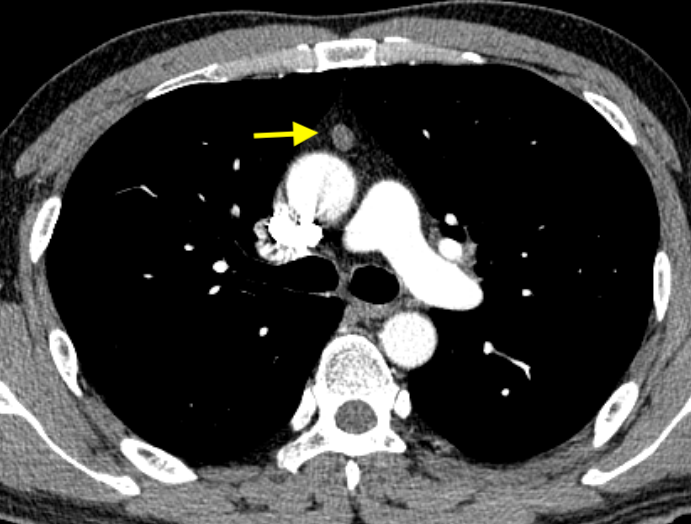

近期科內(nèi)做了一臺縱隔結(jié)節(jié)的微創(chuàng)手術(shù),術(shù)前CT報告:前縱隔見類圓形結(jié)節(jié),大小約108mm,增強掃描未見明顯強化,邊界清。手術(shù)不復(fù)雜,很順利就做完了,重要的是病理回報:考慮B3型胸腺瘤?。?!這么小的結(jié)節(jié)一般門診都是建議隨診觀察的,這個患者是因為在隨診觀察過程中發(fā)現(xiàn)較前明顯增大了,所以才決定做的手術(shù)。手術(shù)做的很及時,險些漏診。胸腺瘤和胸腺癌統(tǒng)稱胸腺上皮腫瘤,起源于胸腺。前縱隔最常見的原發(fā)腫瘤是胸腺瘤,而胸腺癌則較為罕見。有一小部分的胸腺瘤患者可同時合并其他伴隨疾病,比如重癥肌無力(上眼瞼下垂、吞咽無力、全身沒力氣)、貧血等,患者可能先在神經(jīng)內(nèi)科或血液科就診,做肺CT才發(fā)現(xiàn)有胸腺瘤。除此以外,大多數(shù)患者可無任何癥狀,一般是在體檢時偶然發(fā)現(xiàn)的。那么,針對這種體檢或意外發(fā)現(xiàn)的前縱隔小結(jié)節(jié)該怎樣處理才安全呢?1、建議做胸部增強CT或MRI明確結(jié)節(jié)是實性的還是囊性的,胸部MRI在鑒別結(jié)節(jié)是胸腺瘤、胸腺囊腫或胸腺增生方面更有優(yōu)勢;2、如果考慮是胸腺囊腫可以6個月復(fù)查,如果沒問題以后6-12個月復(fù)查,隨診觀察即可,可不做手術(shù);3、如果是實性結(jié)節(jié),考慮胸腺瘤可能,建議手術(shù);如果結(jié)節(jié)較小,邊緣清晰,剛發(fā)現(xiàn),也可以選擇密切隨訪觀察,6個月內(nèi)復(fù)查是安全的,隨訪過程中若結(jié)節(jié)有增長,及時手術(shù);4、能外科手術(shù)的胸腺腫瘤,應(yīng)避免穿刺活檢取病理,因為穿刺活檢使腫瘤包膜受侵后有很大播種轉(zhuǎn)移風險。雖然胸腺瘤都是惡性的,但早期的胸腺瘤微創(chuàng)手術(shù)就可解決,而且手術(shù)切除后預(yù)后一般都很好,大家不用過于擔心。